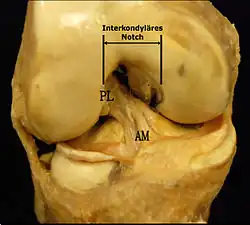

Anatomische Faktoren gehören zu den schon länger vermuteten Risikofaktoren. Die Reißfestigkeit eines Kreuzbandes hängt unmittelbar mit dessen Breite zusammen, die wiederum von Mensch zu Mensch unterschiedlich sein kann. In einer anthropometrischen Studie wurden die vorderen Kreuzbänder des unverletzten kontralateralen Knies von Patienten mit einer Kreuzbandruptur mit denen einer Kontrollgruppe mit gleicher mittlerer Körpermasse verglichen. Die Volumina der Kreuzbänder wurden mittels Magnetresonanztomografie ermittelt. In der Gruppe mit Kreuzbandrissen betrug das Volumen des kontralateralen Kreuzbandes durchschnittlich 1921 mm³, während es bei der Kontrollgruppe bei 2151 mm³ lag. Die Autoren der Studie schließen daraus, dass anthropometrische Unterschiede im Volumen – und daraus abgeleitet der Breite – des Kreuzbandes einen direkten Einfluss auf die Wahrscheinlichkeit eines Kreuzbandrisses ohne Fremdeinwirkung haben.[48] Schon in früheren Studien wurde eine Korrelation von einer schmalen Kreuzbandhöhle (interkondyläres Notch), die wiederum im Zusammenhang mit einem schmaleren Kreuzband steht, mit einem erhöhten Risiko für einen Kreuzbandriss festgestellt.[49][50][51][52][53][54] Allerdings herrscht darüber kein wissenschaftlicher Konsens, da andere Studien zu anderen Ergebnissen kommen.[42][55][56] Frauen haben gegenüber Männern eine schmalere Kreuzbandhöhle, weshalb dieser anatomische Unterschied ein Erklärungsmodell für die höhere Inzidenz von Kreuzbandrupturen bei Frauen ist.[57][58]